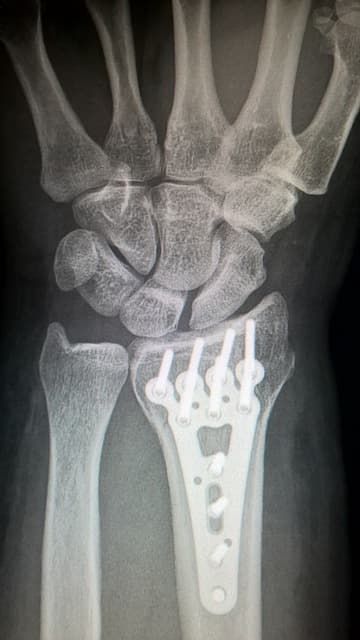

- 인공 관절(Artificial Joint)

- 티타늄 합금과 폴리에틸렌은 인공 관절의 주요 소재로 사용되며, 높은 생체적합성과 내구성을 제공합니다.

- 예: 고관절 및 무릎 관절 대체 수술에 사용되는 인공 관절.